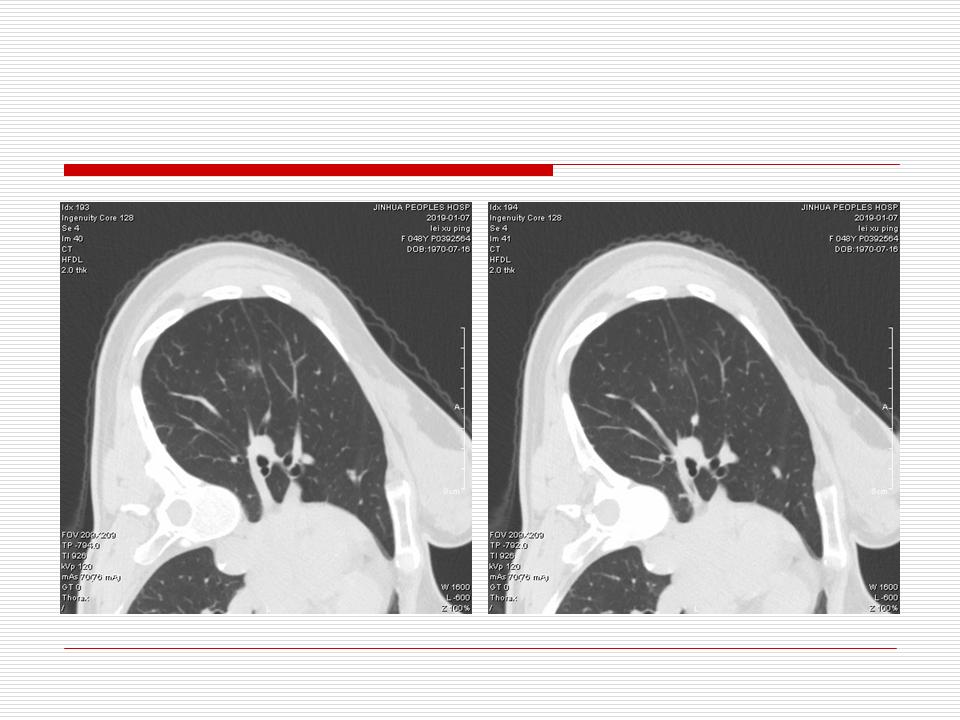

肺部阴影永恒且最重需要鉴别的是:到底是炎症还是肿瘤?但临床的病例中的影像表现难以界定或有些肿瘤特征,同时又有些炎症特点是非常常见的情况。作为临床医生我们怎么去总结分析,并找到之所以是炎症或之所以是肿瘤的细微差别或特点非常重要,也非常有用。2019.12.7浙江省2019年胸心外科学学术年会在宁波召开时,我的临床病例分析与经验总结<那些像肺癌的炎症与像炎症的肺癌>获得在大会交流的机会,以下为该PPT的内容,与你分享,希望对同道有益,有借鉴与启迪。若有探讨与进一不完善的建议,欢迎文末留言讨论: